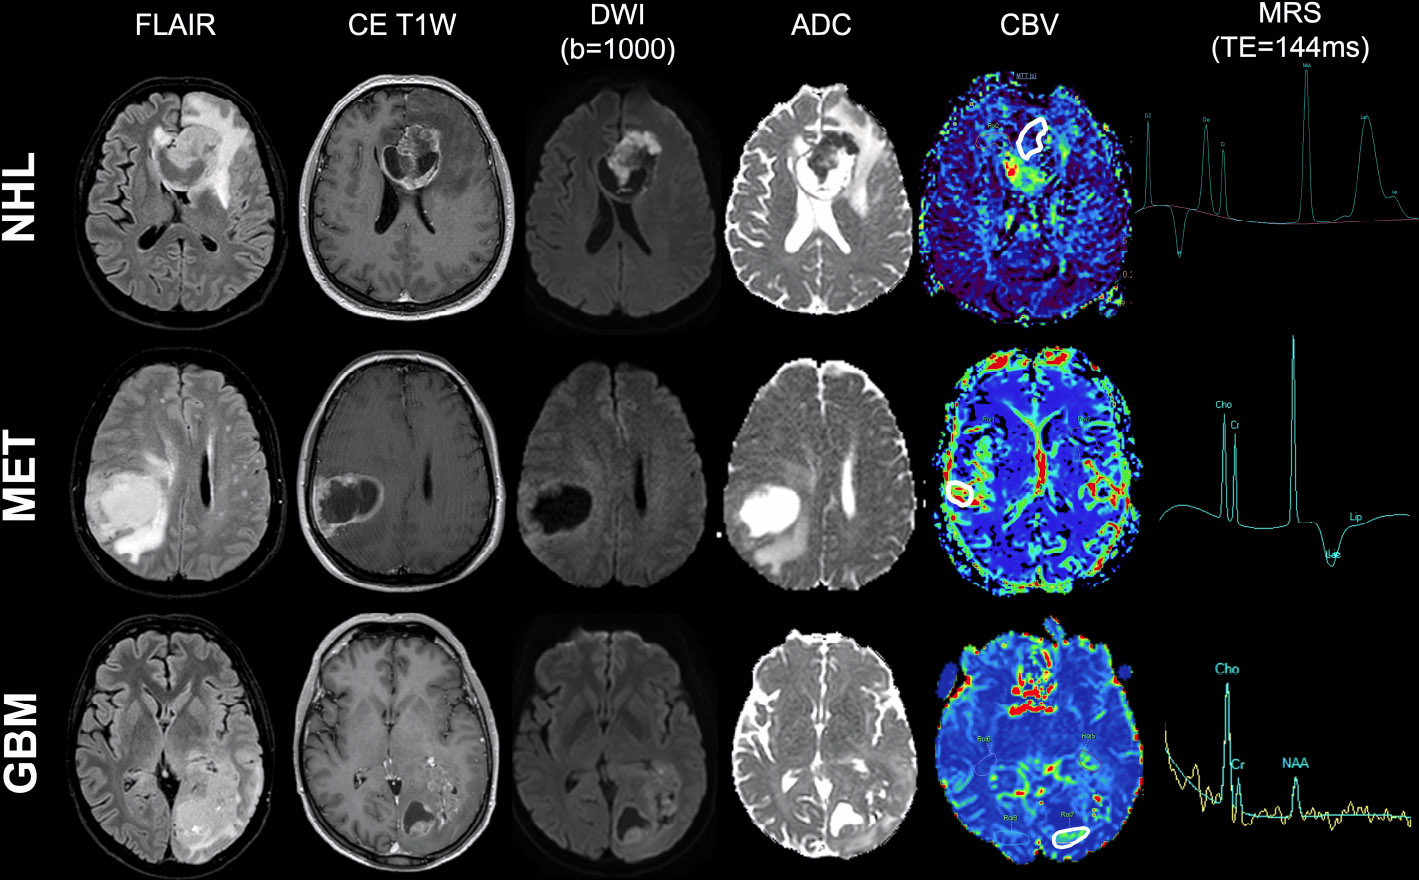

Example of conventional MRI findings in the three most common adult brain tumor types. Three examples of conventional MRI findings in non-Hodgkin lymphoma (first row), single brain metastasis (second row), and wild-type glioblastoma (third row): A) FLAIR imaging; B) post-contrast T1w imaging; C) b-1000 DWI and D) relative ADC map; E) CBV map from DSC-PWI, with ROI placement (white continuous line); F) MRS metabolite spectrum (TE=144 ms).

MRI DICOM data from each examination were anonymized and locally stored. Quantitative variables derived from DWI, PWI, and MRS acquisitions encompassed: ADC values from the DWI sequence; CBV, CBF, MTT, and TTP values within the specific ROI from the DSC PWI acquisition; metabolite peaks, such as lipid-lactates (Lip-Lac), N-acetylaspartate (NAA), choline (Cho), and creatine (Cr), with their ratios from MRS acquisition. To minimize information loss, the above-mentioned quantitative variables derived from DWI, PWI, and MRS acquisitions were analyzed and plotted using CA [13]. PCA was performed for dimensionality reduction and exploratory data analysis, as it transforms a set of possibly correlated variables into a smaller set of uncorrelated variables called principal components (PCs). These components are linear combinations of the original variables and are ordered so that the first component captures the maximum possible variance in the data, the second captures the maximum remaining variance orthogonal to the first, and so on. Before PCA, variables were standardized by calculating their means and standard deviations, and then applying the standardization formula z = (x−μ)/σ. To determine how many PC to retain, a scree plot graph was obtained. To determine whether the differences among the three groups (NHL, GBM, and MET) were significant, the Kruskal-Wallis test was used. Finally, for relevant parameters, between-groups differences (NHL vs. GBM, GBM vs. MET, and MET vs. NHL) were tested using the Wilcoxon signed-rank test. An original p-value of less than 0.01 was set, followed by Bonferroni correction to adjust for multiple comparisons. For all analyses, a final significance level of p = 0.0011 (Bonferroni-corrected) was established. Statistical analyses were performed using the XLStat package v.2019. An example of an MRI of the three malignant brain lesions included in the analysis is shown in Fig. (1). Demographic data and the prevalence of final histological diagnoses in our sample are summarized in Table 1.